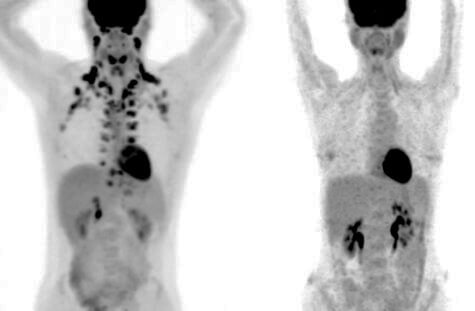

Mỡ nâu có thể giúp người trưởng thành giảm các bệnh mãn tính